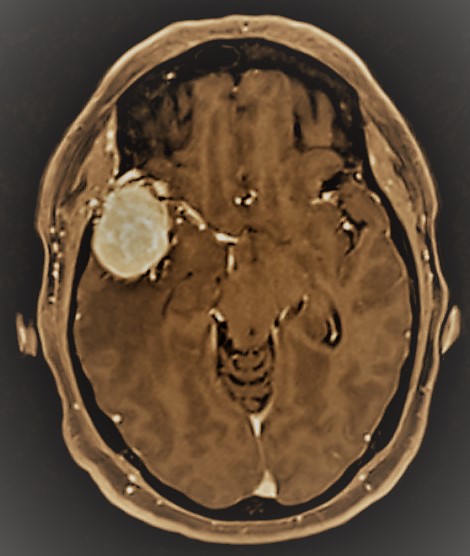

Tratamiento microquirúrgico de tumores cerebrales

Con una metodología de trabajo definida por nuestro firme compromiso con:

1. Seguridad del paciente

2. Planificación quirúrgica

3. Excelencia en la técnica microquirúrgica

4. Compromiso con el conocimiento científico